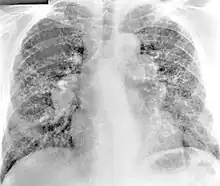

Chest radiography findings of berylliosis are non-specific. Early in the disease radiography findings are usually normal. In later stages interstitial fibrosis, pleural irregularities, hilar lymphadenopathy and ground-glass opacities have been reported.[20][21] Findings on CT are also not specific to berylliosis. Findings that are common in CT scans of people with berylliosis include parenchymal nodules in early stages. One study found that ground-glass opacities were more commonly seen on CT scan in berylliosis than in sarcoidosis. In later stages hilar lymphadenopathy, interstitial pulmonary fibrosis and pleural thickening.[21]